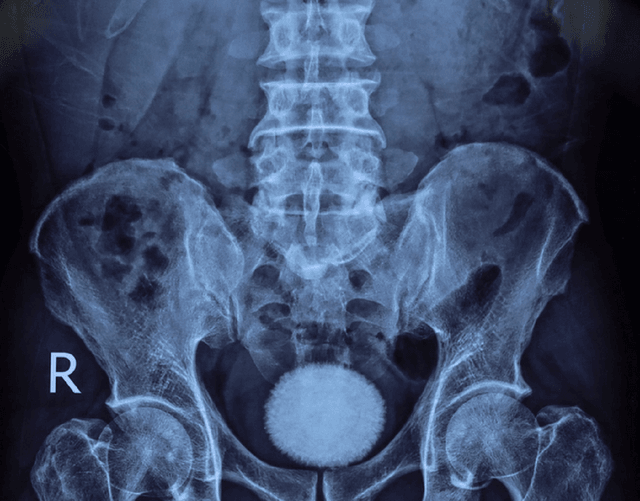

Khai thác tiền sử bệnh trước đó, bệnh nhân đến khám trong tình trạng tiểu buốt, tiểu khó kéo dài, kèm đau vùng hạ vị. Qua thăm khám lâm sàng, siêu âm và chụp X-quang, các bác sĩ phát hiện trong bàng quang có viên sỏi kích thước khoảng 60x40 mm.

Trong quá trình phẫu thuật, các bác sĩ rạch da đường giữa trên xương mu, tiếp cận bàng quang và lấy ra một viên sỏi lớn, kích thước tương đương quả trứng ngỗng. Sau khi lấy sỏi, bàng quang được bơm rửa sạch và khâu phục hồi theo đúng quy trình chuyên môn. Ca mổ diễn ra thuận lợi. Hiện bệnh nhân tỉnh táo, sức khỏe ổn định và đang được theo dõi, chăm sóc hậu phẫu.